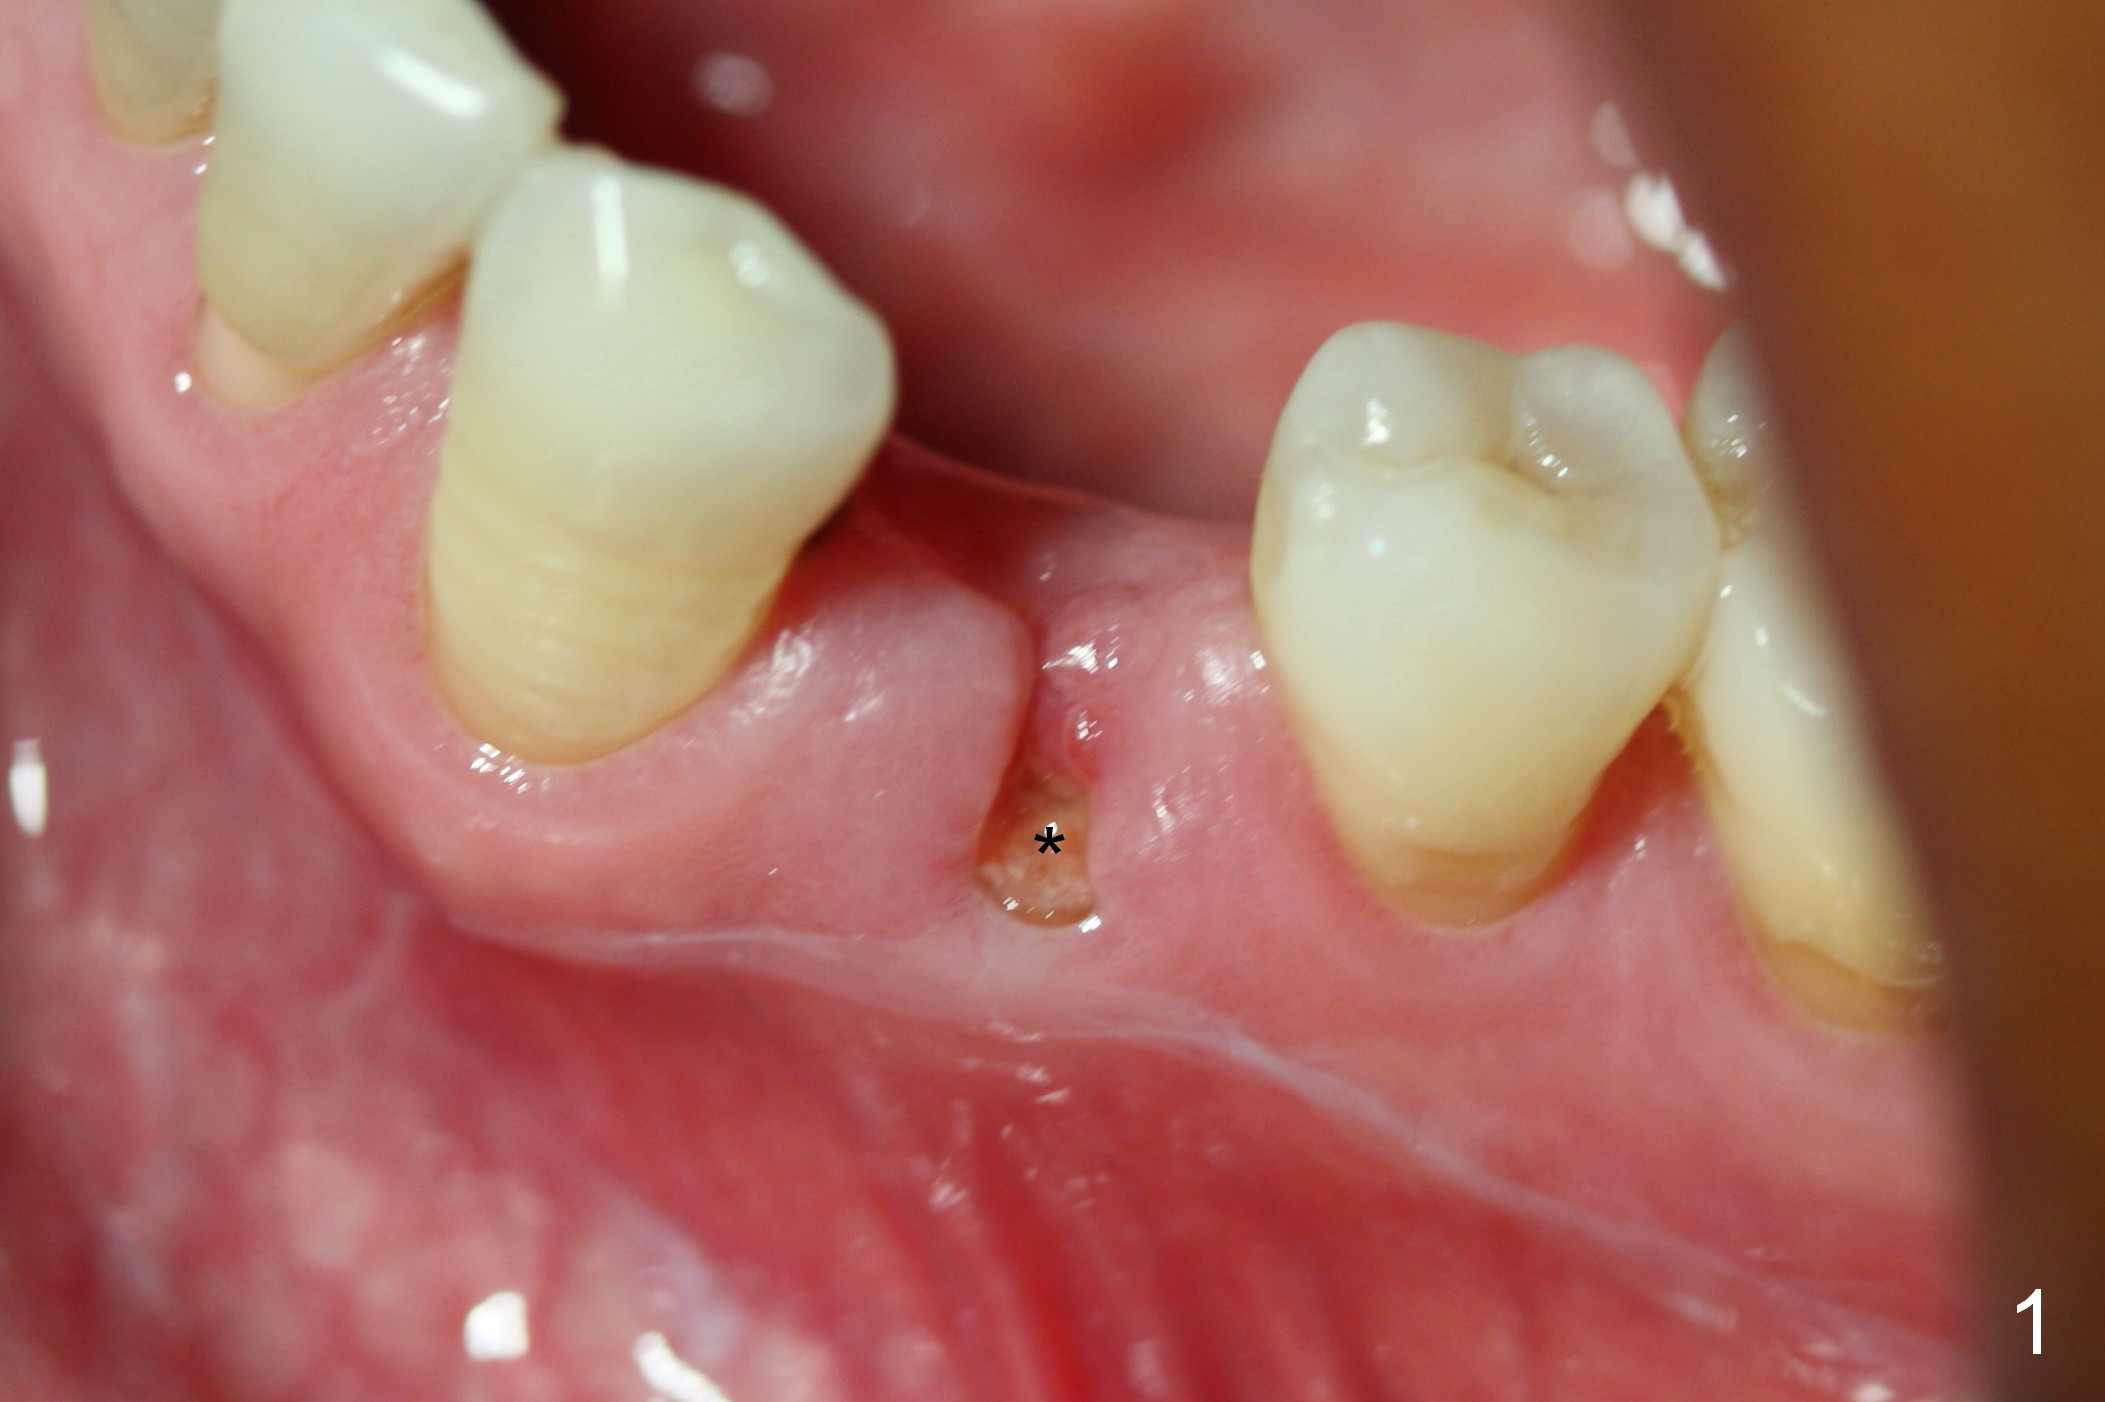

The implant seems to have osteointegrated 4 months postop (Fig.9). When a permanent crown is fabricated, it should have normal occlusal and buccal contour (from Fig.11 (provisional) to 12 red and black curved lines) as well as the buccal cervical extension (Fig.12 to cover the buccal gingiva (Fig.10 *). If the lingual margin of the abutment is too prominent, return the case and the abutment will be changed to the one with 2 mm cuff (existing 3 mm). The lingual margin of the abutment will be trimmed. The patient is not pleased with the short buccal margin of the crown after cementation (Fig.13). In fact the provisional should have been fabricated so that the its buccal margin should be subgingival and within the gingival outline. It may prevent buccal plate collapse. In fact the crown dislodges 1 year post cementation. The lingual margin is prep lower to increase the abutment height. Impression is taken. Although the access hole is unnecessary for cementation, it acts as an escape hole so that there is no excess cement cervically (Fig.14-18).